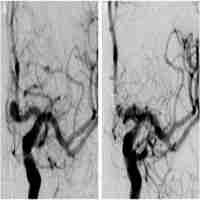

| Abstract | Flow diversion (FD) is a treatment option for recurrent aneurysms including following stent-assisted coiling (SAC), although this approach is both 'off-label' and unproven. A technical challenge of FD placement may involve the microwire catching on the tines of the previously placed stent or potentially going 'in-out-in' from the central axis of the stent. We report a case and technique that assures the wire has safely remained within the central axis of the stent. The procedure was performed in standard fashion except that the intermediate catheter was passed completely through the previously placed stent after the microwire/microcatheter had crossed. The large diameter of the intermediate catheter assured that the microwire did not go 'in-out-in'. The intermediate catheter was completely withdrawn from the stent and the FD was placed in standard fashion. This technique may help to achieve complete FD opening and prevent thromboembolic complications associated with incomplete FD opening. |